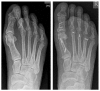

The terminology 'Morton's neuroma' may represent a simplification of the clinical condition as the problem may not be a benign tumour of the nerve, but neuropathic foot pain associated with the interdigital nerve.Foot and ankle pathomechanics leading to metatarsalgia, clinical examination and differential diagnosis of the condition and imaging of the condition, for differential diagnosis, are discussed.Nonoperative management is recommended initially. Physiotherapy, injections (local anaesthetic, steroid, alcohol), cryotherapy, radiofrequency ablation and shockwave therapy are discussed.Operative treatment is indicated after nonoperative management has failed. Neuroma excision has been reported to have good to excellent results in 80% of patients, but gastrocnemius release and osteotomies should be considered so as to address concomitant problems.Key factors in the success of surgery are correct diagnosis with recognition of all elements of the problem and optimal surgical technique. Cite this article: EFORT Open Rev 2019;4:14-24. DOI: 10.1302/2058-5241.4.180025.